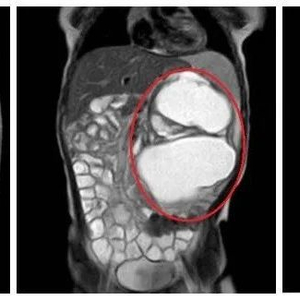

细心的妈妈赶紧带着她到柳城县妇幼保健院检查。B超结果显示,慧慧的肚子里长了一个约14cm×8.5cm×10cm的肿瘤,大小如同一个小苹果。

肿瘤占据腹腔大部分空间

需要尽快手术

“慧慧的肿瘤很大,已经占据了腹腔很多空间,如不及时处理,会压迫邻近脏器。如瘤体压近消化道会出现肠梗阻;推挤膈肌会出现呼吸困难;如与消化道相通时可出现瘘,瘤体还可发生感染引起感染症状。”

慧慧的小肚皮不过排球大小,而肚子里的肿瘤,几乎占据了腹部的大部分位置,把肠子都挤到了右侧腹部,把左肾挤到右下腹,把脾脏推向左上腹部。肿瘤周围遍布重要脏器及血管。